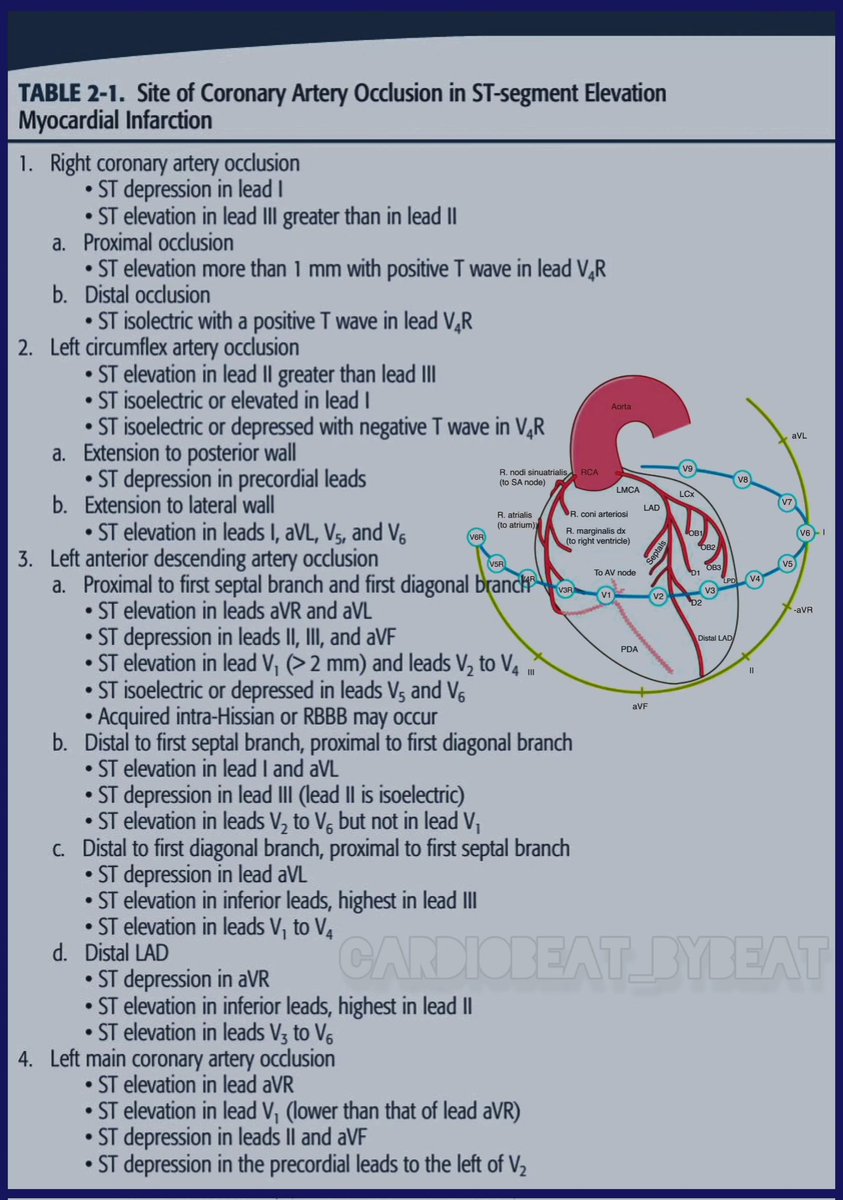

facebook.com/share/p/1CwBAH… 📉ECG Localization of the Culprit Artery in STEMI: Key Patterns ✨ A refined guide for precise localization: #CardioEd #Cardiology #STEMI #ECG #Ischemia #EMCard

facebook.com/share/p/1CwBAH… 📉ECG Localization of the Culprit Artery in STEMI: Key Patterns ✨ A refined guide for precise localization: #CardioEd #Cardiology #STEMI #ECG #Ischemia #EMCard